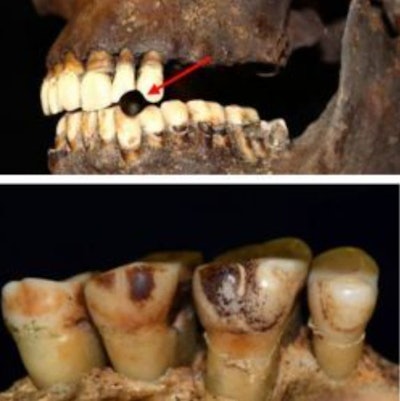

Top: Example of pipe notch (arrowed) [SK134130, St. James’ Gardens Burial Ground, Euston, London (Image reprinted from Davies-Barrett A., Inskip S. under a CC BY license, with permission from Manchester University Press, original copyright 2024)]. Bottom: Example of staining due to smoking [SK417, Holy Trinity Church, Coventry (Image reprinted from Davies-Barrett A., Inskip S. under a CC BY license, with permission from Manchester University Press, original copyright 2024)].

In the study, 46 people undergoing dental treatment that required tooth extraction donated 70 teeth and their medical and smoking histories. Additionally, the team compared the modern teeth against 18 teeth dating from 1776 to 1890. Among the older teeth, the researchers found evidence of smoking, including staining and notches in the teeth from pipe smoking.